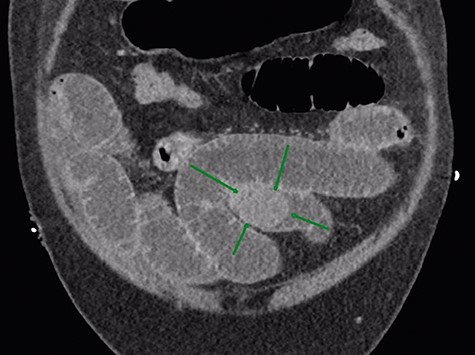

Given that the patient was clinically well, he was managed conservatively overnight with a nasogastric tube and intravenous fluid therapy. The CT scan was closely reviewed by the surgical team the following day and noted the presence of gas within the gallbladder, which was not commented upon by the radiologist (Fig. 2). Furthermore, SBO transition point appeared to be in the distal ileum, where a 3-cm “soft tissue” mass was seen (Fig. 3). His previous CT scan that diagnosed his chronic cholecystitis demonstrated a 3-cm gallstone within the gallbladder, which was not seen on the current CT. The findings of gas within the gallbladder in the setting of SBO and a mass of similar size to the known gallstone raised the suspicion for gallstone ileus. The patient then underwent a laparotomy and enterotomy for a 43-mm gallstone impacted in the distal ileum (Fig. 4). Apart from an episode of ileus, he made a full recovery post-operatively and was discharged home, with an outpatient follow-up in the surgical clinic.